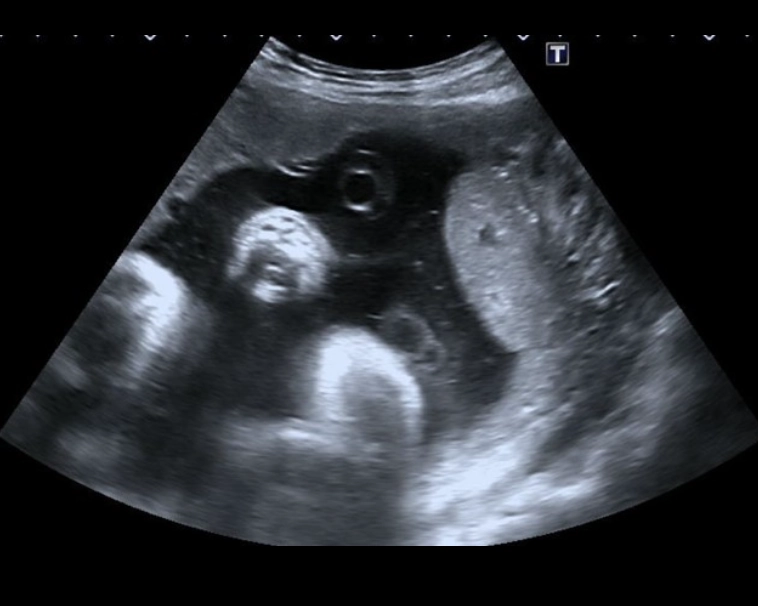

Tổng quan bánh nhau và dây rốn (Approach to the Placenta and Umbilical Cord)

Nhau bong non (Placental Abruption)

Nhau tiền đạo (Placenta Previa) / Nhau bám thấp (Low-Lying Placenta)

Nhau cài răng lược (Placenta Accreta Spectrum - PAS)

Hồ huyết bánh nhau và huyết khối gai nhau (Placental Lakes & Intervillous Thrombus)

Nhau phụ (Succenturiate Lobe)

Nhau cuộn mép (Circumvallate Placenta)

U máu bánh nhau (Chorioangioma)

U quái bánh nhau (Placental Teratoma)

Loạn Sản Trung Mô Bánh Nhau (Placental Mesenchymal Dysplasia - PMD)

Bánh nhau dày (Placentomegaly)

Nang bánh nhau (Placental Cysts)

Dây rốn bám mép / Dây rốn bám màng (Marginal Placental Cord Insertion / Velamentous Cord Insertion)

Dây rốn một động mạch (Single Umbilical Artery - SUA)

Giãn tĩnh mạch rốn thai nhi (Umbilical Vein Varix - UVV)

Tồn Tại Tĩnh Mạch Rốn Phải thai nhi (Persistent Right Umbilical Vein - PRUV)

Xoắn dây rốn (Umbilical Cord Coiling)

Dây rốn thắt nút (True Umbilical Cord Knot)

Mạch máu tiền đạo (Vasa Previa )

Nang dây rốn (Umbilical Cord Cysts)

Huyết khối mạch máu rốn (Umbilical Vessel Thrombosis)